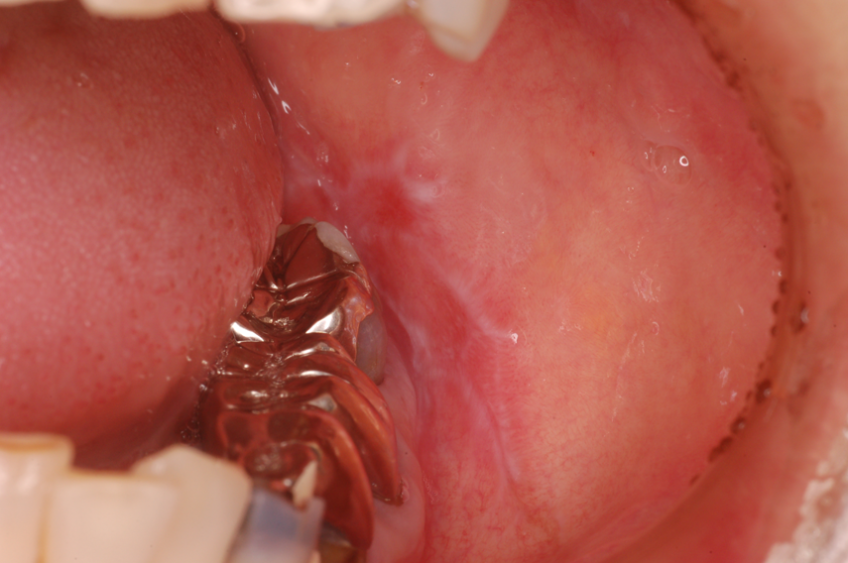

左側頬粘膜扁平苔癬

金属冠と相対する左側頬粘膜に発現した隆起状の扁平苔癬